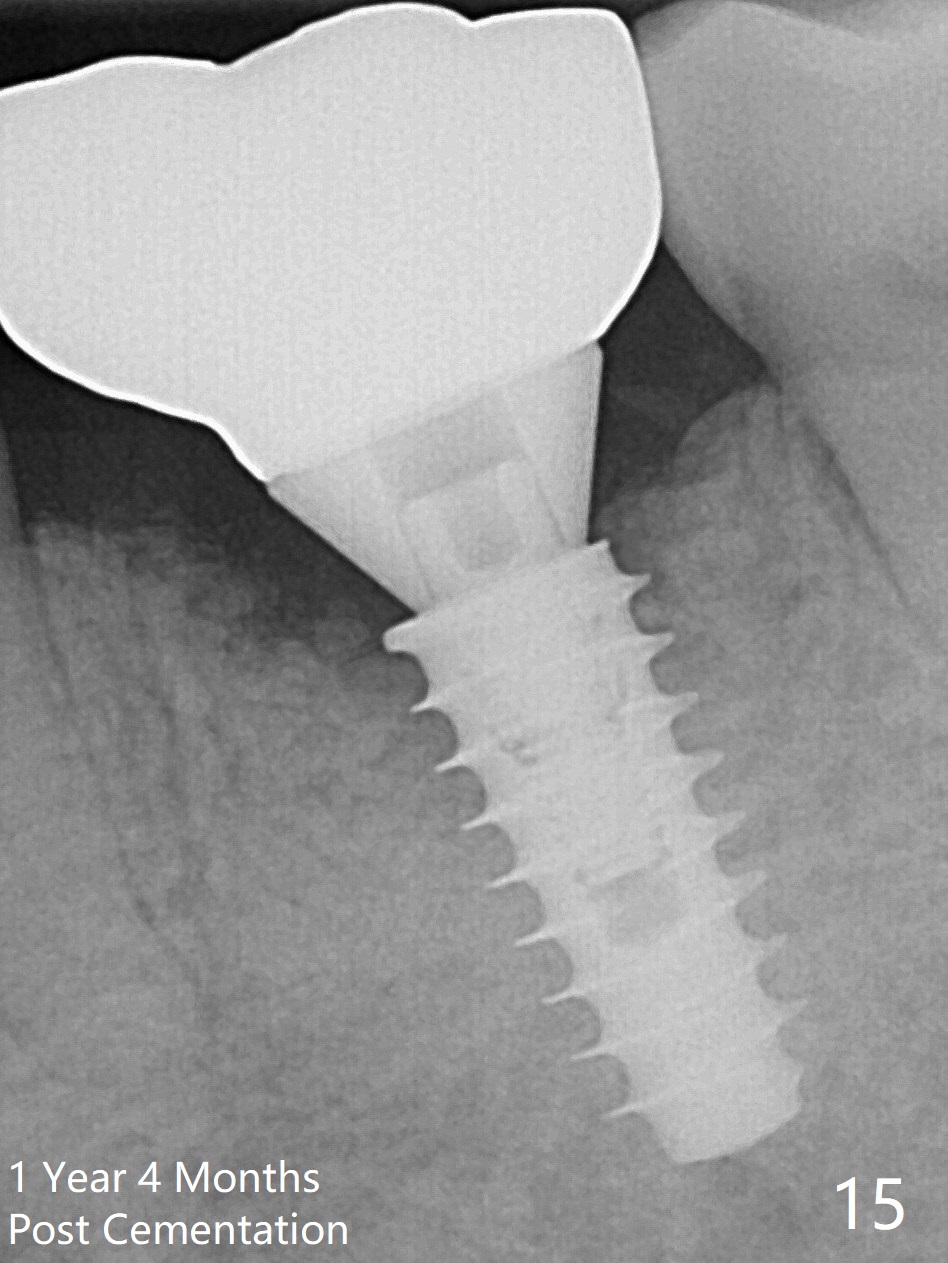

There is a new pattern of bony trabeculae around the implant 4.5 months postop (Fig.14). Bone density increases 1 year 4 months post cementation (Fig.15).